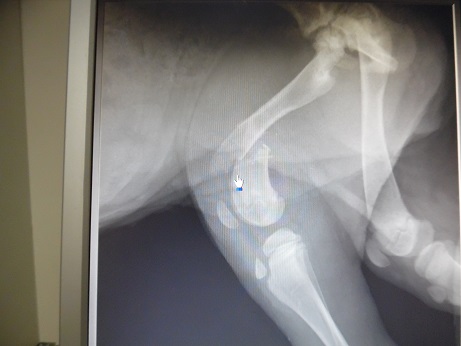

H μικρούλα, μια κουταβίνα 3,5 μηνων. Εμφανίσθηκε στους Γαργαλιάνους με έντονη ψώρα και αδυναμία. Μαζί με όλα, χτυπηθηκε από αυτοκίνητο και έχει σπασμένο μηριαίο.

This little one, a puppy approx 3.5 months old. She was found in Gargalianous area , Pelloponisos, really weak and with scabies. Along with all these she was also hit by a Car and she has broken femur.